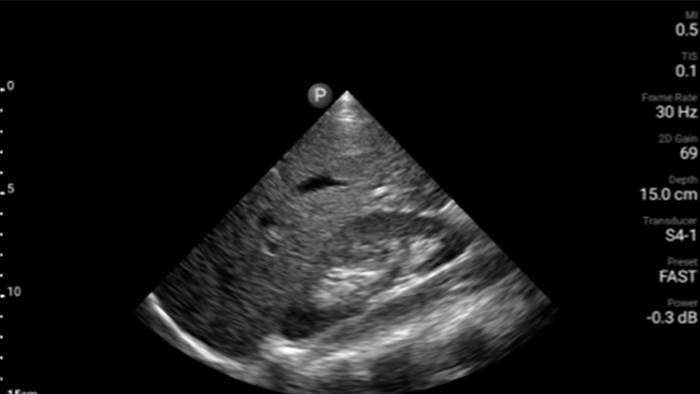

Focused Assessment with Sonography in Trauma (FAST) exam (Sonographische Bestimmung freier Flüssigkeit im Bauchraum (FAST-Untersuchung))